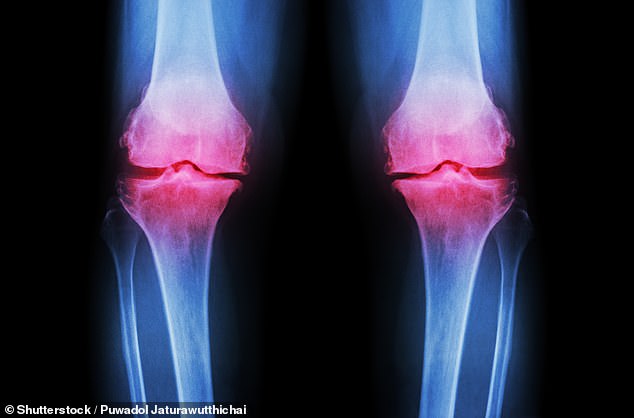

Moreover, the bones begin to weaken during this time, putting individuals at greater risk of fractures later in life. The Royal Osteoporosis Society has highlighted that peak bone health is reached by the age of 30. However, bone density declines with time. If action is not taken in the 40s, individuals may develop osteopenia, the early stage of bone thinning that can lead to osteoporosis. Research shows that up to 40 percent of over-50s may suffer from this condition. This is a growing public health crisis, with experts from the Academic Centre for Healthy Ageing at Queen Mary University of London, Professor Hamish Simpson, warning that many individuals may not be aware they are suffering from bone thinning until they experience a fracture.

To prevent this, experts recommend adopting a healthy lifestyle. According to Dr. Richie Abel of the Bone Health Research Group at Imperial College London, eating well, reducing alcohol intake, and increasing physical activity can significantly reduce the risk of future fractures. He also emphasizes the importance of a calcium-rich diet, where possible, and taking vitamin D supplements. Professor Simpson adds that physical activity is the most effective intervention, especially for bone health. 'Any increase in activity is beneficial, but for bones in particular you want loading exercises - jumping or skipping - which create the small shocks that stimulate bone growth,' he explains.